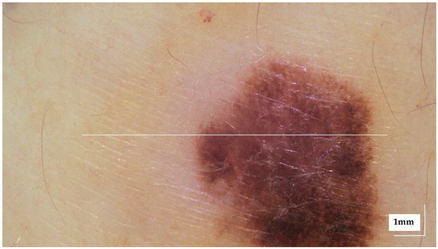

| Superficial spreading melanoma (SSM) Case 2 | Localization: right forefoot (right ankle) |

![]() | ![]() |